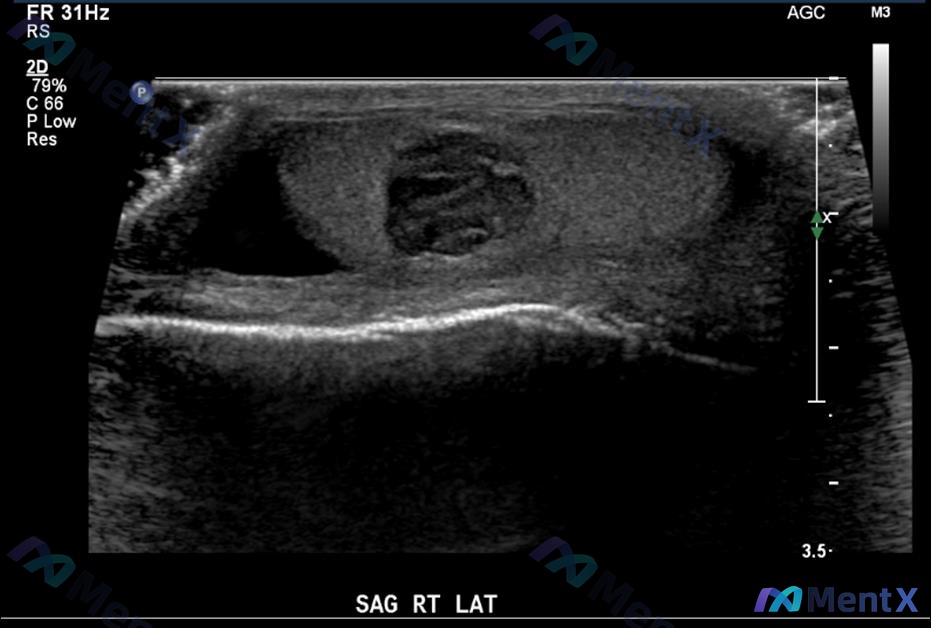

10岁男孩水肿1个月,大量蛋白尿但血压高到这个程度,第一诊断还会是单纯肾病吗?

整理到一份儿童肾脏病例,第一眼有点容易被带偏,放出来大家一起理理思路: > 基本情况:10岁男孩 > 主诉:水肿1个月 > 查体:BP 130/95mmHg,颜面和四肢水肿,心肺未见异常 > 实验室检查:血BUN 10mmol/L,尿蛋白(+++),24小时尿蛋白定量 2.5g 另外还有两个延伸问题...